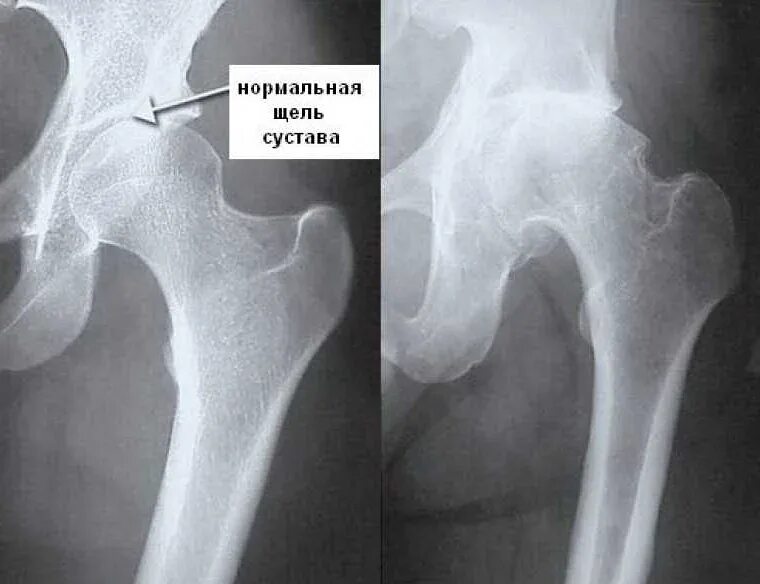

Коксартроз тазобедренного 1 стадии